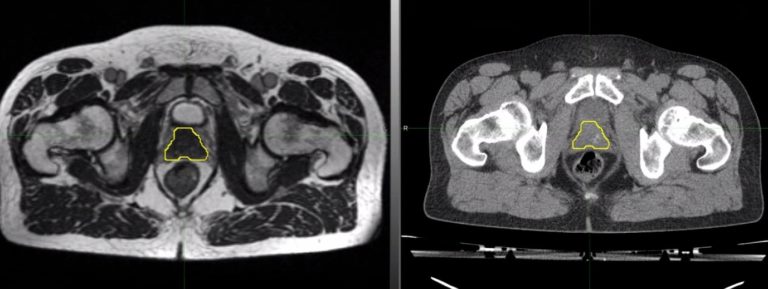

The MRIdian planning process allows prostate delineation on a hybrid MR (magnetic resonance) scan (A). This taken alongside a planning CT (computerised tomography) scan (B) and diagnostic MR scan provides clear images for contouring the prostate. Traditionally, prostate radiotherapy has been planned by outlining the prostate on a CT scan (B), using additional information from a diagnostic MR scan.

A Hybrid MR scan used for planning MRIdian -based radiotherapy, with prostate delineated (yellow contour)

B Standard Planning CT scan used for conventional radiotherapy for the same patient, with prostate delineated (yellow contour)